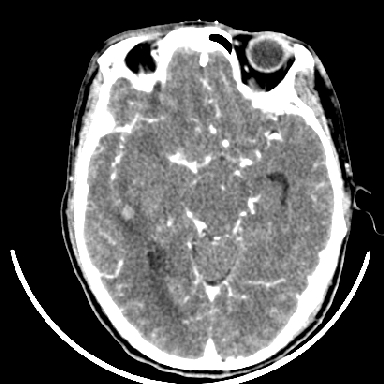

标题: CT6056:脑出血(血管畸形?) [打印本页]

标题: CT6056:脑出血(血管畸形?)

m 40突发头痛左侧偏瘫3小时

考虑高血压性脑出血,依据:

1是高血压性脑出血的好发部位,形态呈肾形,是高血压性脑出血的常见形状

2增强时占位效应加重了,考虑出血还没有停止

3病灶周围水肿不是太厉害,一般肿瘤出血水肿多非常明显

4病灶周围的‘软组织’影没有明显的强化

5至于脑血管畸形引起的出血,暂时没有看到明显的畸形血管影,也不太支持

另附部分资料:“血液溢出血管外形成血肿,其内含有大量血红蛋白、血浆白蛋白,球蛋白,因这些蛋白对x线的吸收系数高于脑质,故ct呈现高密度阴影,ct值达40~90h,最初高密度灶呈非均匀一致性,中心密度更高,新鲜出血灶边缘不清。基底节区血肿多为“肾”型,内侧凹陷,外侧膨隆,因外侧裂阻力较小,故向外凸,其它部位血肿多呈尖圆形或不规则形”

术中抽出40ml陈旧血液,血肿底部似见一条索血管影